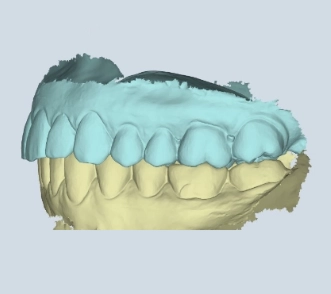

Mit der digitalen 4D-Funktionsdiagnostik erfassen wir Ihren Biss und die Kiefergelenkfunktion in Bewegung, um intelligentere und stabilere Behandlungen zu planen – besonders bei CMD und komplexen Fällen.

Mit unserer digitalen Funktionsanalyse erfassen wir Ihre Kieferfunktion in 4D-Bewegung, um Behandlungen zu entwickeln, die sich genauso gut anfühlen wie sie aussehen. Schnell und strahlungsfrei – für detaillierte Einblicke in Biss, Kiefergelenke und Kaufunktion in Echtzeit und in Zeitlupe.

Sehen Sie genau, wie sich Ihr Unterkiefer in Echtzeit bewegt – und Probleme entdecken, die statische Messungen übersehen.

Bevor eine Behandlung beginnt, nutzen wir das Echtzeit-Kiefertracking, um genau zu sehen, wie Ihr gesamter Kauapparat in Bewegung funktioniert.

Wir beginnen mit einer digitalen 4D-Funktionsdiagnostik, um zu erfassen, wie sich Ihr Kiefer in Echtzeit bewegt. Schnell, berührungslos und strahlungsfrei – für einen vollständigen Blick auf Biss, Gelenke und Funktion. Kein Rätselraten. Nur Klarheit.

Jedes Lächeln erzählt eine Geschichte – und Ihr Kiefer auch. Mit unserer digitalen 4D-Diagnostik sehen Sie, wie Ihr gesamter Kauapparat funktioniert, bevor wir starten – und was wir verbessern sollten.